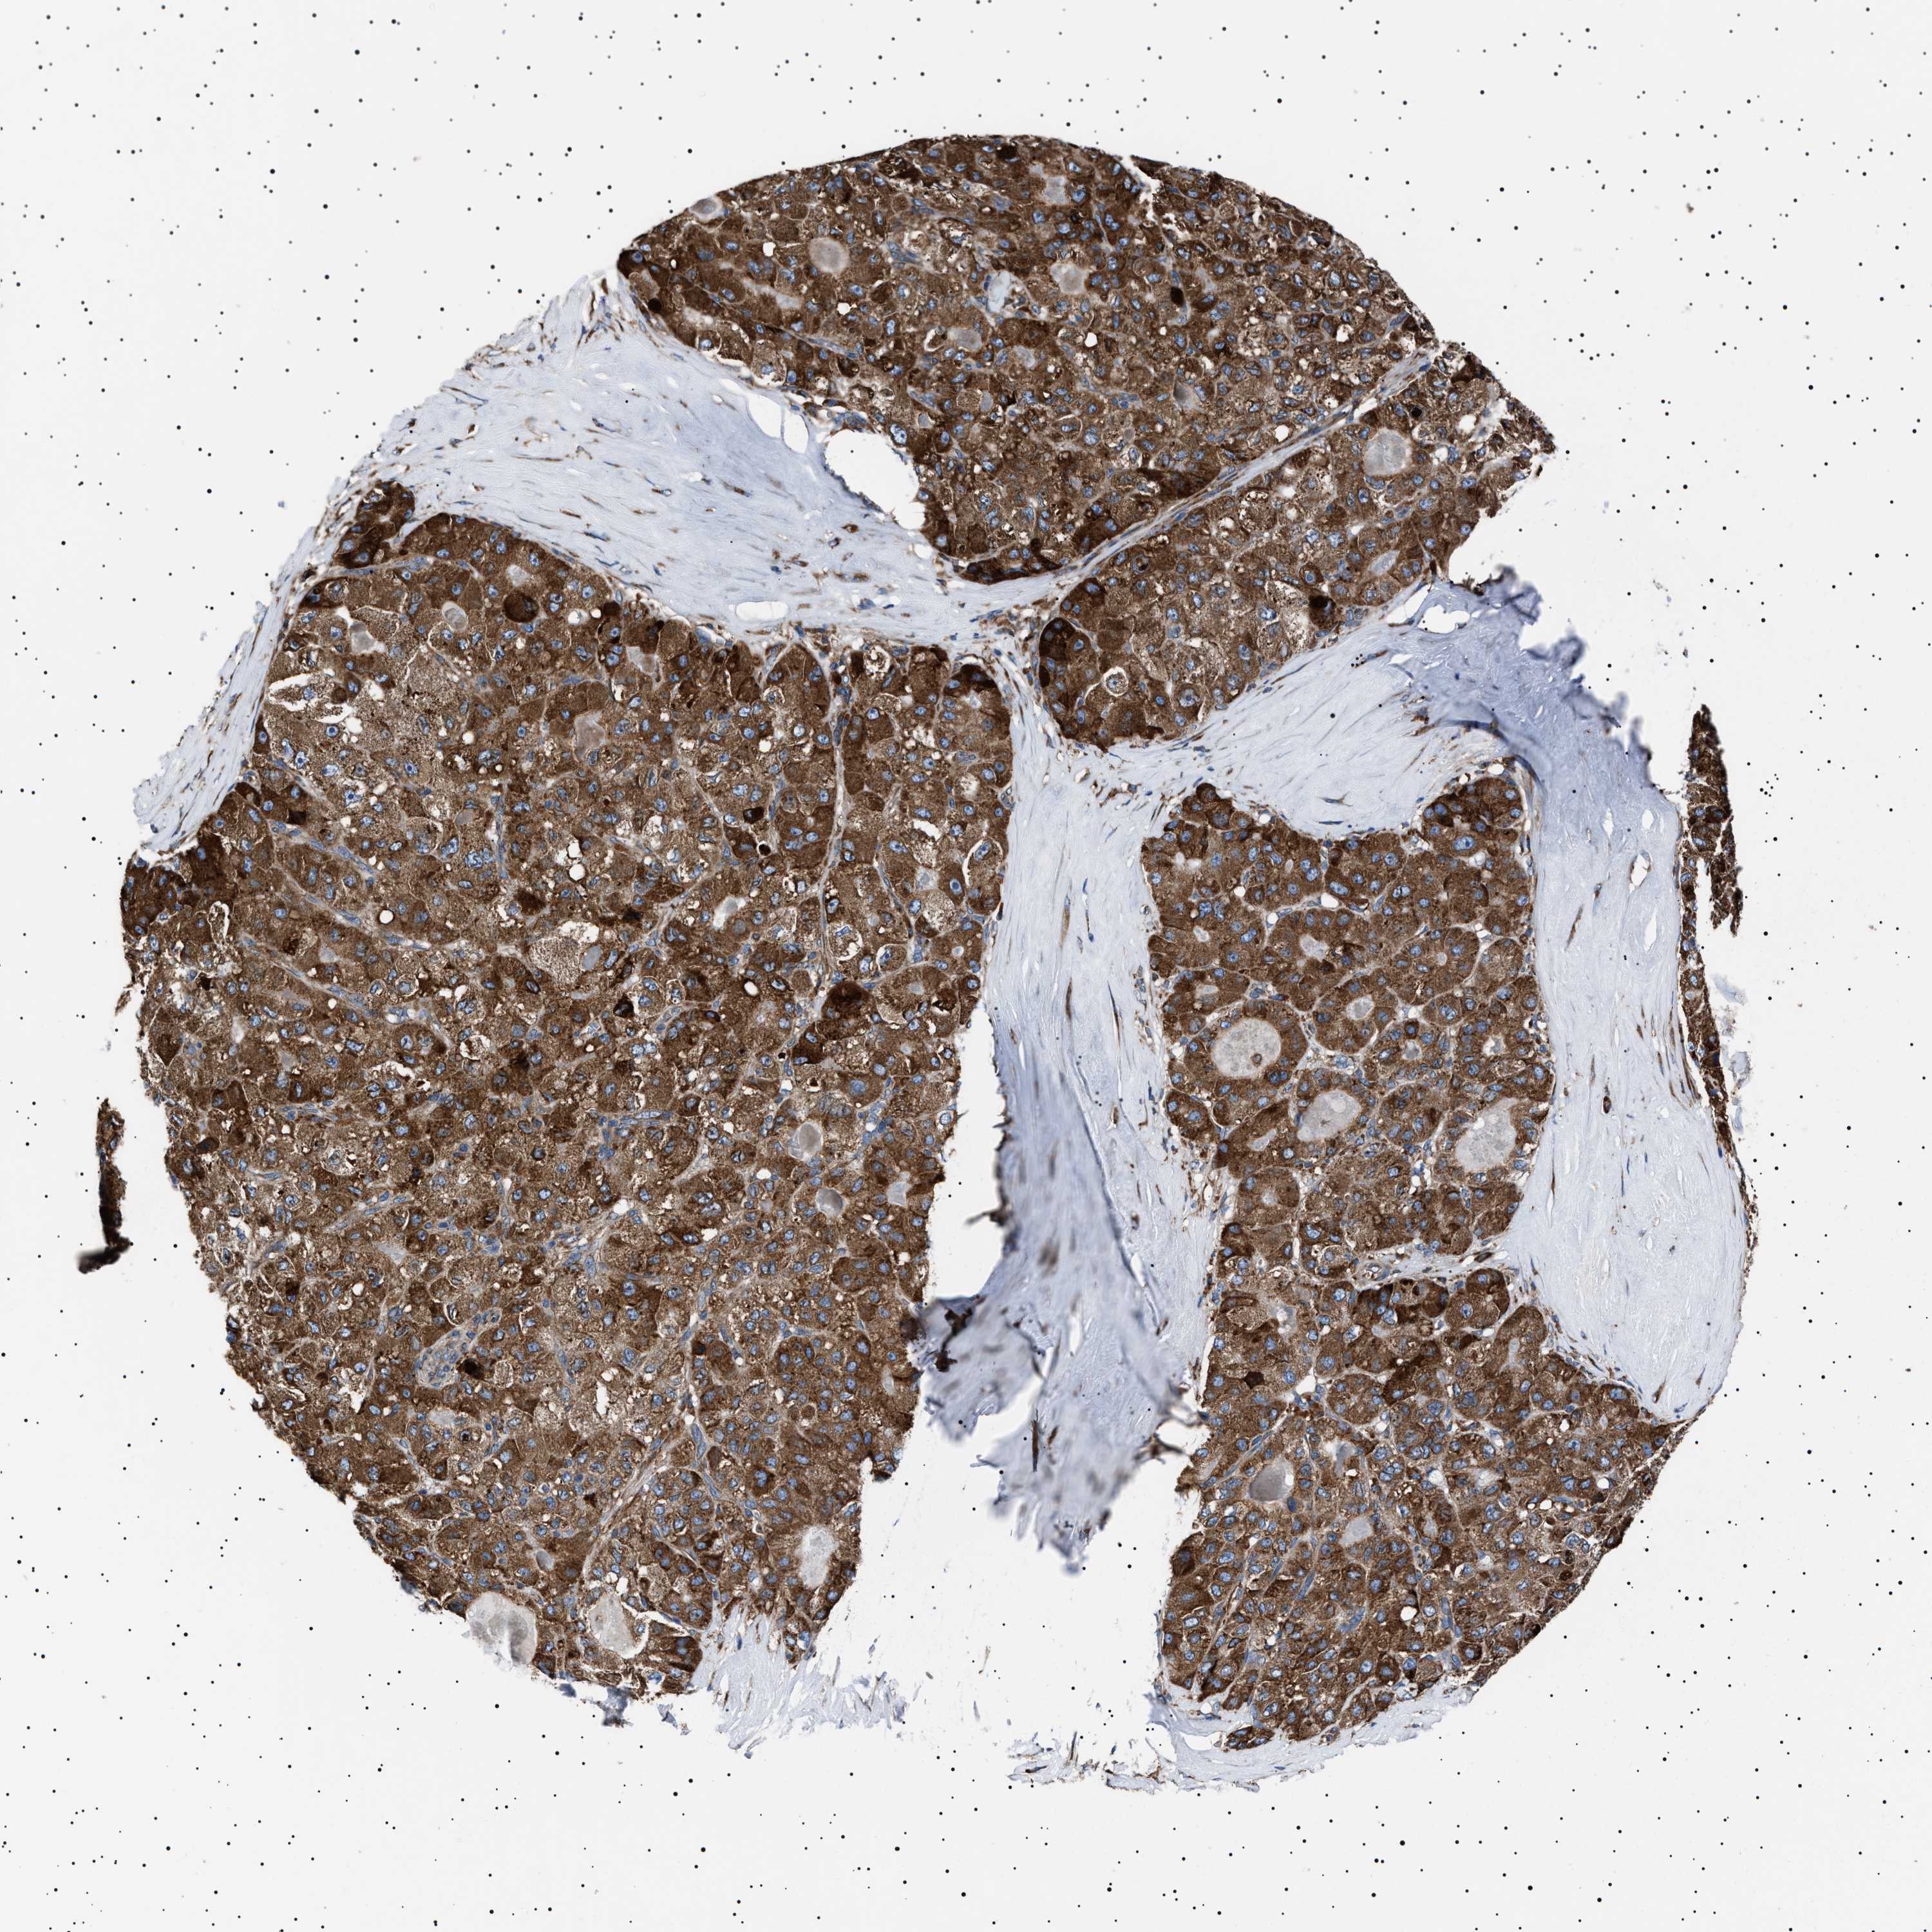

LIVER CANCER - Protein expressioni

A mouse-over function shows sample information and annotation data. Click on an image to view it in a full screen mode. Samples can be filtered based on level of antibody staining by selecting one or several of the following categories: high, medium, low and not detected. The assay and annotation is described here.

Note that samples used for immunohistochemistry by the Human Protein Atlas do not correspond to samples in the TCGA dataset.

Antibody stainingi

Antibody staining in the annotated cell types in the current human tissue is reported as not detected, low, medium, or high, based on conventional immunohistochemistry profiling in selected tissues. This score is based on the combination of the staining intensity and fraction of stained cells.

Each image is clickable and will lead to virtual microscopy that enables deeper exploration of all samples and also displays staining intensity scores, fraction scores and subcellular localization as well as patient and tissue information for each sample.

Antibody HPA001915

Antibody HPA021542

Staining

High

Medium

Low

Not detected

Intensity

Strong

Moderate

Weak

Negative

Quantity

>75%

75%-25%

<25%

None

Location

Nuclear

Cytoplasmic/membranous

Cytoplasmic/membranous,nuclear

Cholangiocarcinoma

Carcinoma, Hepatocellular, NOS